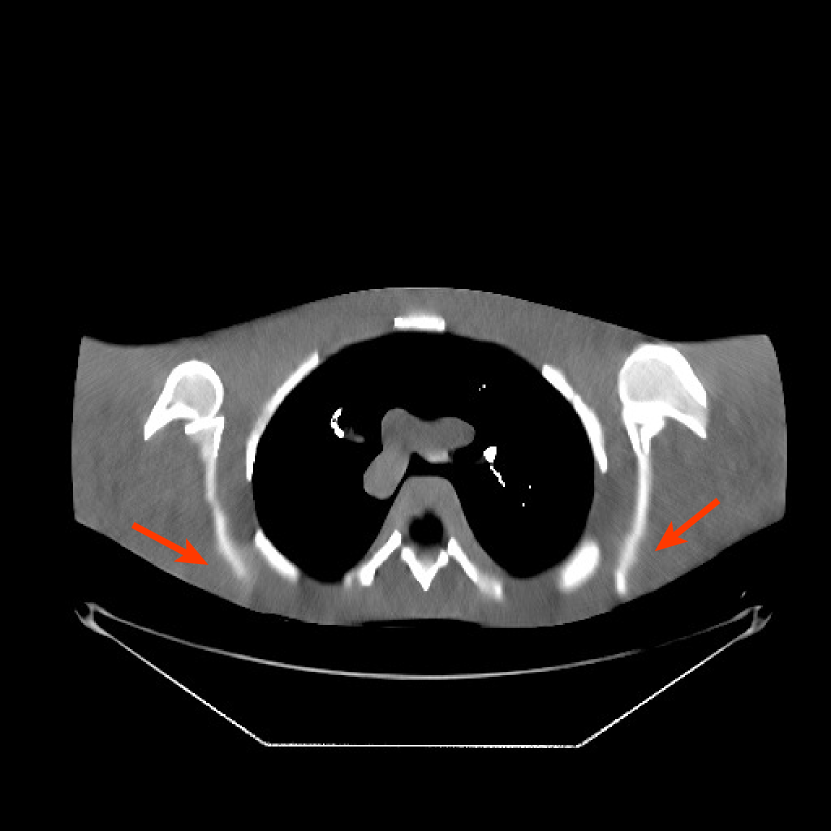

Fig. 9 shows three axial slices from the 3D reconstructions with SPULTRA and PWLS-ULTRA at : the middle slice (No. 67) and two slices located farther away from the center (No. 90 and No. 120). The image profiles along a horizontal line (shown in green) in the displayed slices are also shown in Fig. 9. The reconstructed slices using PWLS-ULTRA appear darker around the center compared to the “true” clinical image and the reconstructions with SPULTRA. This means PWLS-ULTRA produces a strong bias in the reconstruction. The bias can be observed more clearly in the profile plots: the pixel intensities for the SPULTRA reconstruction better follow those of the “true” clinical image, while those for the PWLS-ULTRA reconstruction are much worse than the “true” values. Moreover, SPULTRA achieves sharper rising and failing edges compared to PWLS-ULTRA. In other words, SPULTRA also achieves better resolution than PWLS-ULTRA. Fig. 9 also shows a zoomed-in ROI for each of the chosen slices, and highlights some small details with arrows. It is clear that in addition to reducing the bias, SPULTRA reconstructs image details better than PWLS-ULTRA.